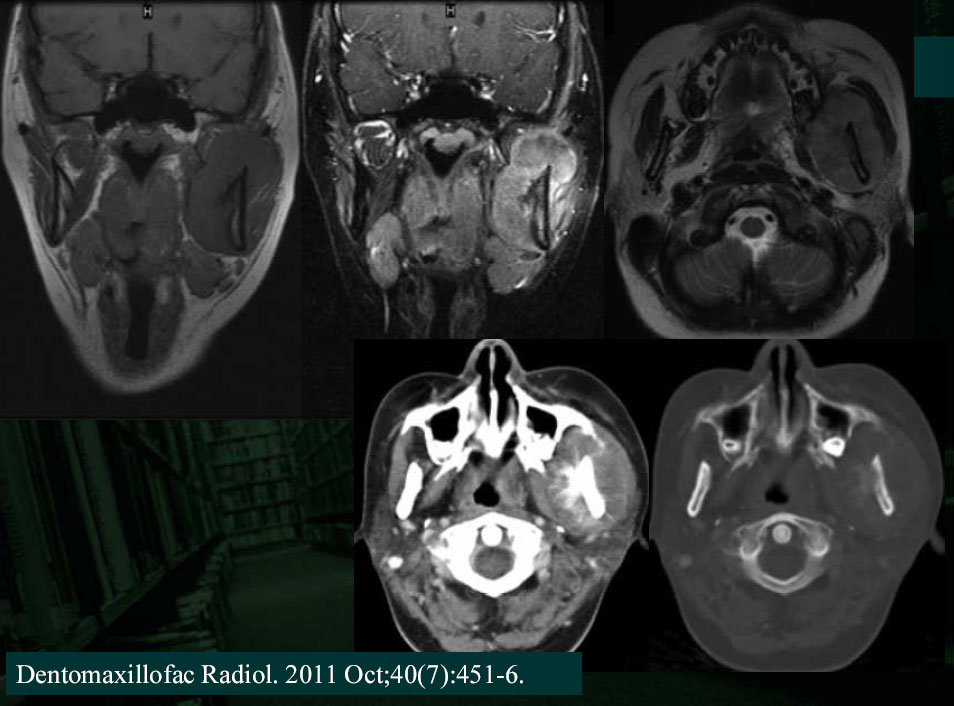

Peripheral PNET occurs outside the central and sympathetic nervous system, often occurs in the thoracopulmonary region (Askin tumor),retroperitonium, and extremities and rarely in the head and neck.

The imaging features of pPNET of the head and neck

are nonspecific.

In pPNET patients with tumors originating from soft tissues, the tumors often demonstrated ill-defined,soft tissue masses and exhibited aggressive spreading to the neighboring tissue.

The tumor often demonstrated isodensity with patchyhypodensity areas on unenhanced CT images.

On T1WI, the tumor demonstrated isointensity or slightly hypointensity; on T2WI, the tumor demonstrated heterogeneous hyperintensity.

The tumor demonstrated heterogeneous enhancement on contrast-enhanced CT/T1WI.

Calcification is rare.

Cystic necrotic component and haemorrhagic change are usually obvious.